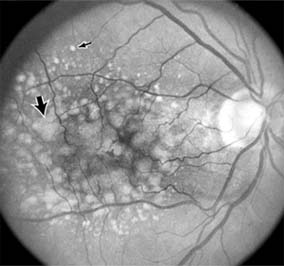

Chapter 10: Retina DISEASES OF THE MACULA AGE-RELATED MACULAR DEGENERATION Age-related macular degeneration is the leading cause of permanent blindness in the elderly. The exact cause is unknown, but the incidence increases with each decade over age 50. Other associations besides age include race (usually Caucasian), sex (slight female predominance), family history, and a history of cigarette smoking. The disease includes a broad spectrum of clinical and pathologic findings that can be classified into two groups: nonexudative ("dry") and exudative ("wet"). Although both types are progressive and usually bilateral, they differ in their manifestations, prognosis, and management. The more severe exudative form accounts for approximately 90% of all cases of legal blindness due to age-related macular degeneration. 1. NONEXUDATIVE MACULAR DEGENERATION Nonexudative age-related macular degeneration is characterized by variable degrees of atrophy and degeneration of the outer retina, retinal pigment epithelium, Bruch's membrane and choriocapillaris. Of the ophthalmoscopically visible changes in the retinal pigment epithelium and Bruch's membrane, drusen are the most typical (Figure 10-1). Drusen are discrete, round, yellow-white deposits of variable size beneath the pigment epithelium and are scattered throughout the macula and posterior pole. With time, they may enlarge, coalesce, calcify, and increase in number. Histopathologically, most drusen consist of focal collections of eosinophilic material lying between the pigment epithelium and Bruch's membrane; they therefore represent focal detachment of the pigment epithelium. In addition to drusen, clumps of pigment irregularly dispersed within depigmented areas of atrophy may progressively appear throughout the macula. The level of associated visual impairment is variable and may be minimal. Fluorescein angiography demonstrates irregular patterns of retinal pigment epithelial hyperplasia and atrophy. Electrophysiologic testing in most patients is normal. There is no generally accepted treatment or means of prevention of this type of macular degeneration. Laser retinal photocoagulation appears to have a beneficial effect on drusen but has not yet been shown to improve visual outcome. Although high plasma levels of antioxidants are associated with a reduced risk of age-related macular degeneration, the use of vitamin supplements does not appear to be preventive. Most patients with macular drusen never experience significant loss of central vision; the atrophic changes may stabilize or progress slowly. However, the exudative stage may develop suddenly at any time, and in addition to regular ophthalmic examinations, patients are given an Amsler grid ( 2. EXUDATIVE MACULAR DEGENERATION Although patients with age-related macular degeneration usually manifest nonexudative changes only, the majority of patients who experience severe vision loss from this disease do so from the development of subretinal neovascularization and related exudative maculopathy. Serous fluid from the underlying choroid can leak through small defects in Bruch's membrane, causing focal detachment of the pigment epithelium. Additional fluid may lead to further separation of the overlying sensory retina, and vision usually decreases if the fovea is involved. Retinal pigment epithelial detachments may spontaneously flatten, with variable visual results, and leave a geographic area of depigmentation at the involved site. Ingrowth of new vessels from the choroid into the subretinal space is the most important change that predisposes patients with drusen to macular detachment and irreversible loss of central vision. These new vessels grow in a flat cartwheel or sea-fan configuration away from their site of entry into the subretinal space. The clinical changes of early subretinal neovascularization are subtle and may be easily overlooked; during this occult stage of new vessel formation, the patient is asymptomatic, and the new vessels may not be apparent either ophthalmoscopically or angiographically. The ophthalmologist must maintain a high index of suspicion that subretinal neovascularization is present whenever a patient with evidence of age-related macular degeneration has sudden or recent central vision loss, including blurred vision, distortion, or a new scotoma. If the fundus examination reveals subretinal blood, exudate, or a grayish-green choroidal lesion in the macula, there is great likelihood that neovascularization is present, and a fluorescein or indocyanine green angiogram should be obtained promptly to determine if a treatable lesion can be identified. Although some subretinal neovascular membranes may spontaneously regress, the natural course of subretinal neovascularization in age-related macular degeneration is toward irreversible loss of central vision over a variable period of time. The sensory retina may be damaged by long-standing edema, detachment, or underlying hemorrhage. Furthermore, a hemorrhagic detachment of the retina may undergo fibrous metaplasia, resulting in an elevated subretinal mass called a disciform scar. This elevated fibrovascular mound of variable size represents the cicatricial end stage of exudative age-related macular degeneration. It is usually centrally located and results in permanent loss of central vision. Treatment In the absence of subretinal neovascularization, no medical or surgical treatment of serous retinal pigment epithelial detachment is of proved benefit. The use of parenteral alpha interferon, for example, has not been effective for this disease. However, if a well-defined extrafoveal ( Krypton laser photocoagulation of juxtafoveal (<200 Following successful photocoagulation of a subretinal neovascular membrane, recurrent neovascularization either contiguous with or remote from the laser scar may occur in one-half of cases by 2 years. Recurrence is often accompanied by severe vision loss, so that careful monitoring with Amsler grids, ophthalmoscopy, and angiography is essential. Low-dose radiotherapy has provided encouraging results in patients with subfoveal neovascularization. Patients with impaired central vision in both eyes may benefit from a variety of low vision aids. CENTRAL SEROUS CHORIORETINOPATHY Central serous chorioretinopathy is characterized by serous detachment of the sensory retina as a consequence of focal leakage of fluid from the choriocapillaris through a defect in the retinal pigment epithelium (Figures 10-2 and 10-3). This disease typically affects young to middle-aged men and may be related to life stress events. Most patients present with the sudden onset of blurred vision, micropsia, metamorphopsia, and central scotoma. Visual acuity is often only moderately decreased and may be improved to near-normal with a small hyperopic correction. The diagnosis is made by slitlamp examination of the fundus; the presence of serous detachment of the sensory retina in the absence of ocular inflammation, subretinal neovascularization, an optic pit, or a choroidal tumor is diagnostic. The retinal pigment epithelial lesion appears as a small, round or oval, yellowish-gray spot that is variable in size and may be difficult to detect without the aid of fluorescein angiography. Fluorescein dye leaking from the choriocapillaris may accumulate below the pigment epithelium or sensory retina, resulting in a variety of patterns including the well-recognized smokestack configuration. Approximately 80% of eyes with central serous chorioretinopathy undergo spontaneous resorption of subretinal fluid and recovery of normal visual acuity within 6 months after the onset of symptoms. Despite normal acuity, however, many patients have a mild permanent visual defect, such as a decrease in color sensitivity, micropsia, or relative scotoma. Twenty to 30 percent of patients will have one or more recurrences of the disease, and complications-including subretinal neovascularization and chronic cystoid macular edema-have been described in patients with frequent and prolonged serous detachments. The cause of central serous chorioretinopathy is unknown; there is no convincing evidence that the disease is either infectious or due to retinal pigment epithelial dystrophy. Argon laser photocoagulation directed to the active leak significantly shortens the duration of the sensory detachment and hastens the recovery of central vision, but there is no evidence that prompt photocoagulation reduces the chance of permanent loss of visual function. Although the complications of retinal laser photocoagulation are few, it is probably not advisable to recommend immediate photocoagulation treatment in all patients with central serous chorioretinopathy. The duration and location of disease, the condition of the fellow eye, and occupational visual requirements are all considerations upon which treatment decisions are based. MACULAR EDEMA Retinal edema involving the macula may be associated with a variety of intraocular inflammatory diseases, retinal vascular diseases, intraocular surgery, inherited or acquired retinal degenerations, medications, macular membranes, or unknown causes. Macular edema may be diffuse, with nonlocalized intraretinal fluid causing thickening of the macula. When edema fluid accumulates in honeycomb-like spaces of the outer plexiform and inner nuclear layers, it is called cystoid macular edema. On fluorescein angiography, fluorescein dye leaks from the perifoveal retinal capillaries and accumulates in a flower-petal pattern about the fovea (Figure 10-4). The most widely recognized association with cystoid macular edema is intraocular surgery. Approximately 50% of eyes undergoing uneventful intracapsular cataract extraction and 20% of eyes undergoing extracapsular cataract extraction develop angiographic cystoid macular edema. Clinically significant edema usually occurs within 4-12 weeks postoperatively, but in some instances its onset may be delayed for months or years. Many patients with cystoid macular edema of less than 6 months' duration have self-limited leakage that will resolve without treatment. Topical or local (or both) anti-inflammatory therapy may be of value in restoring visual acuity in some patients with chronic postoperative macular edema. YAG laser vitreolysis (see Chapter 24) and surgical vitrectomy may be of benefit when the macular edema is associated with vitreous tissue incarcerated in the cataract wound or adherent to anterior segment structures. When an intraocular lens implant is the cause of postoperative macular edema due to its design, positioning, or inadequate fixation, removal of the lens implant can be considered. INFLAMMATORY DISORDERS INVOLVING THE MACULA Presumed Ocular Histoplasmosis Syndrome (Figures 10-5, 10-6 and 10-7) In this disease, serous and hemorrhagic detachments of the macula are associated with multiple peripheral atrophic chorioretinal scars and peripapillary chorioretinal scarring (see Chapter 7). The syndrome usually occurs in healthy patients between the third and sixth decades of life, and the scars are probably caused by an antecedent subclinical systemic infection with Histoplasma capsulatum. The macular detachments are due to subretinal neovascularization, and the visual prognosis depends on the proximity of the neovascular membrane to the center of the fovea. If the membrane extends inside the foveal avascular zone, only 15% of eyes will retain 20/40 vision. A macular scar may change over time, and 10% of patients with normal maculae will develop new atrophic scars in this region. The relative risk of developing macular subretinal neovascularization in the second eye of an affected patient is significant, and these patients should be instructed in the frequent use of the Amsler grid and the importance of prompt examination when changes are detected. Argon laser photocoagulation of a subretinal neovascular membrane outside the foveal avascular zone in symptomatic patients is of value in preventing severe vision loss. The surgical removal of submacular membranes may prove useful in preserving vision. Acute Multifocal Posterior Placoid Pigment Epitheliopathy (AMPPPE) AMPPPE typically affects healthy young patients who develop rapidly progressive bilateral vision loss in association with ophthalmoscopically visible multifocal flat gray-white subretinal lesions involving the pigment epithelium (Figure 10-8). The cause of this disease, which in many instances is associated with evidence of an influenza-like illness, is unknown; the course and nature of the illness suggests the possibility of viral infection. The characteristic feature of the disease is the rapid resolution of the fundus lesions and a delayed return of visual acuity to near-normal levels. Although the prognosis for visual recovery in this acute self-limited disease is good, many patients will identify small residual paracentral scotomas when carefully tested. Extensive pigmentary changes remaining during the late stages of AMPPPE may mimic widespread retinal degeneration; the clinical history and normal electrophysiologic findings aid in this differential diagnosis. Geographic Helicoid Peripapillary Choroidopathy This is a chronic progressive and recurrent multifocal inflammatory disease of the retinal pigment epithelium, choriocapillaris, and choroid. It characteristically involves the juxtapapillary retina and extends radially to involve the macula and peripheral retina. The active stage manifests itself as sharply demarcated gray-yellow lesions with irregular borders that appear to involve the pigment epithelium and choriocapillaris. Vitritis, anterior uveitis, and subretinal neovascularization have been associated with this disorder. Involvement is usually bilateral, and the cause is unknown. The natural history of this indolent inflammatory disease is variable and may correlate with the presence of disease in the fellow eye. Local or systemic corticosteroid treatment may be of benefit when active inflammation is present; laser photocoagulation is administered as indicated for the complication of subretinal neovascularization. Vitiliginous Chorioretinitis (Birdshot Retinochoroidopathy) This is a syndrome characterized by diffuse cream-colored patches at the level of the pigment epithelium and choroid, retinal vasculitis associated with cystoid macular edema, and vitritis. The associations with HLA-A29 and with retinal S-antigen suggest that this disease has a genetic predisposition and that retinal autoimmunity plays a role in its manifestations. In many cases, electroretinography, electro-oculography, and dark adaptation studies are abnormal. The course of the disease is that of exacerbation and remission with variable visual outcomes; visual loss has been attributed to chronic cystoid macular edema, optic atrophy, macular scarring, or subretinal neovascularization. Corticosteroid therapy has not proved effective against this disease. Acute Macular Neuroretinopathy Acute macular neuroretinopathy is characterized by the acute onset of paracentral scotomas and mild visual acuity loss accompanied by wedge-shaped parafoveal retinal lesions in the deep sensory retina of one or both eyes. The macular lesions are subtle, reddish-brown, and best seen with a red-free light. The patients are usually young adults with a history of acute viral illness. While the retinal lesions may fade, the scotomas tend to persist and remain symptomatic. Multiple Evanescent White Dot Syndrome This is an acute and self-limited unilateral disease that affects mainly young women and is characterized clinically by multiple white dots at the level of the pigment epithelium, vitreal cells, and transient electroretinographic abnormalities. The cause is unknown. There is no evidence of associated systemic disease. The retinal lesions gradually regress in a matter of weeks, leaving only minor retinal pigment epithelial defects. ANGIOID STREAKS Angioid streaks appear as irregular, jagged tapering lines that radiate from the peripapillary retina into the macula and peripheral fundus (Figure 10-9). The streaks represent linear crack-like dehiscences in Bruch's membrane. The lesions are rarely noted in children and probably develop in the second or third decade of life. Early in the disease the streaks are sharply outlined and red-orange or brown. Subsequent fibrovascular tissue growth may partially or totally obscure the streak margins. Nearly 50% of patients with angioid streaks have an associated systemic disease. Pseudoxanthoma elasticum, Paget's disease of bone, Ehlers-Danlos syndrome, and several hemoglobinopathies and hemolytic disorders have been associated with this retinal disease, but the most common association is with age-related degeneration of Bruch's membrane. Patients with angioid streaks should be warned of the potential risk of choroidal rupture from even relatively mild eye trauma. Older patients with the disease are at risk of developing serous and hemorrhagic detachments of the retina as a consequence of subretinal neovascularization. Laser treatment may be used to photocoagulate extrafoveal neovascular membranes; however, other neovascular membranes are likely to occur. Prophylactic treatment of angioid streaks before subretinal neovascularization develops is not recommended. MYOPIC MACULAR DEGENERATION Pathologic myopia is one of the leading causes of blindness in the United States and is characterized by progressive elongation of the eye with subsequent thinning and atrophy of the choroid and pigment epithelium in the macula. Peripapillary chorioretinal atrophy and linear breaks in Bruch's membrane ("lacquer cracks") are characteristic findings on ophthalmoscopy (Figure 10-10). The degenerative changes of the macular pigment epithelium resemble those found in the older patient with age-related macular degeneration. A characteristic lesion of this disease is a raised, circular, pigmented macular lesion called a Fuchs spot. Most patients are in the fifth decade when the degenerative macular changes cause a slowly progressive loss of vision; rapid loss of visual acuity is usually caused by serous and hemorrhagic macular degeneration overlying a subretinal neovascular membrane. Fluorescein angiography in patients with pathologic myopia may show delayed filling of choroidal and retinal blood vessels. Angiography is helpful in identifying and locating the site of subretinal neovascularization in patients who develop serous or hemorrhagic detachments of the macula. Because of the frequent close proximity of the subretinal neovascular membrane to the foveola in these patients, laser photocoagulation may not be possible. As subretinal neovascular membranes tend to remain small and because photocoagulation-associated chorioretinal atrophy tends to progress in patients with pathologic myopia, retinal laser treatment is not as beneficial as in other diseases associated with macular subretinal neovascularization. The chorioretinal changes of pathologic myopia predispose the retina to breaks and thus to retinal detachment. Peripheral retinal findings may include paving stone degeneration, pigmentary degeneration, and lattice degeneration. Retinal breaks usually occur in areas involved with chorioretinal lesions, but they also arise in areas of apparently normal retina. Some of these breaks, particularly those of the "horseshoe" and round retinal tear type, will progress to rhegmatogenous retinal detachment. MACULAR HOLE A macular hole is a partial or full-thickness absence of the sensory retina in the macula. This disorder occurs most often in elderly women and is associated with elevated plasma fibrinogen levels. The typical finding on biomicroscopy of the symptomatic eye is a full-thickness, round or oval, sharply defined hole measuring one-third disk diameter in the center of the macula, which may be surrounded by a ring detachment of the sensory retina (Figure 10-11). With a full-thickness macular hole, visual acuity is impaired and metamorphopsia, as well as a central scotoma, are present on the Amsler grid. An operculum of retinal tissue may overlie the macular hole. Tangential traction from epiretinal vitreous cortex plays an important role in the pathogenesis of macular hole. Early stages of macular hole formation, such as a deep foveal yellow spot or ring, may be reversible as the posterior vitreous cortex spontaneously separates from the retina. Therapy for macular hole disease involves reattaching and potentially restoring function to the retina overlying the cuff of subretinal fluid surrounding the hole. While the anatomic results of vitrectomy surgery to close macular holes are encouraging, the clinical benefits are still under study. EPIRETINAL MACULAR MEMBRANES Fibrocellular membranes may proliferate on the surface of the retina, either in the macula or peripheral retina. Contraction or shrinkage of these epiretinal membranes may cause varying degrees of visual distortion, intraretinal edema, and degeneration of the underlying retina. Biomicroscopy usually shows retinal wrinkles and vessel tortuosity and may rarely also show retinal hemorrhages, cotton-wool spots, serous retinal detachment, and macular hole; a posterior vitreous detachment is nearly always present (Figure 10-12). Disorders associated with epiretinal membranes include retinal tears with or without rhegmatogenous retinal detachment, vitreous inflammatory diseases, trauma, and a variety of retinal vascular diseases. Patients with macular distortion and vision loss caused by epiretinal membrane contraction are usually left with stable visual acuity, suggesting that membrane contraction is a short-lived and self-limited process. Surgical peeling of severe epiretinal membranes can be performed successfully, but regrowth of epiretinal tissues occurs in some cases. There is no role for photocoagulation in the treatment of epiretinal macular membrane disease. TRAUMATIC MACULOPATHY Blunt trauma to the anterior segment of the eye may cause a contrecoup injury to the retina called commotio retinae. The retina develops a gray-white color that affects primarily the outer retina and may be confined to the macular area (Berlin's edema) or may involve extensive areas of the peripheral retina. The retinal whitening in the macular area may clear completely, or impairment of central vision may be permanent and associated with a pigmented retinal scar (Figure 10-13) or a macular hole. Trauma similar to that which causes Berlin's edema may also cause choroidal rupture with subretinal hemorrhage and permanent central vision loss. In addition to blunt trauma, several other traumatic injuries involving the macula are of importance. Purtscher's retinopathy is characterized by multiple patches of superficial retinal whitening and retinal hemorrhages in each eye of a patient after severe compression injury to the head or trunk. Terson's syndrome is seen in approximately 20% of patients after traumatic (or spontaneous) subarachnoid or subdural hemorrhage and is characterized by vitreous and superficial macular hemorrhage. Solar retinopathy refers to a specific foveolar lesion that occurs after sun-gazing and is best described as a usually bilateral sharply circumscribed and often irregularly shaped partial-thickness hole or depression in the center of the fovea. MACULAR DYSTROPHIES Macular dystrophies differ from degenerations in that the former are inherited, though not necessarily evident at birth, and are not associated with systemic diseases. Most often the disorder is restricted to the macula; it may be symmetric or asymmetric, but eventually both eyes are affected. In the early stages of some of these disorders the visual acuity may be reduced while the macular changes are subtle or absent on ophthalmoscopy, and the patient's complaint may be dismissed as spurious. Conversely, in other macular dystrophies, the ophthalmoscopic changes may be very striking at a time when the patient is free of visual symptoms. One method of classifying the more common macular dystrophies is to consider the presumptive anatomic layer or layers of the retina involved (Table 10-1). X-Linked Juvenile Retinoschisis This is a congenital disease of males characterized by a macular lesion called "foveal schisis." On slitlamp examination, foveal schisis appears as small superficial retinal cysts arranged in a stellate pattern accompanied by radial striae centered in the foveal area (Figure 10-14). Visual acuity is usually between 20/40 and 20/200; peripheral visual field abnormalities are present in the 50% of patients with associated peripheral retinoschisis. The posterior pole appears normal on fluorescein angiography, and this may be helpful in the clinical differentiation from cystoid macular edema. B wave abnormalities on the electroretinogram are consistent with the histopathologic finding of intraretinal splitting in the nerve fiber layer. Cone-Rod Dystrophies The cone-rod dystrophies constitute a relatively rare group of disorders that may be regarded as a single entity showing variable expressivity. Most cases are sporadic, but familial cases are usually transmitted by an autosomal dominant inheritance pattern. Cone-rod dystrophy is characterized by predominant involvement of the cone photoreceptors with progressive color vision defects and associated loss of visual acuity. A bilateral and symmetric bulls-eye pattern of depigmentation and a corresponding zone of hyperfluorescence surrounding a central nonfluorescent spot (similar to that seen in chloroquine retinopathy) are the most commonly described biomicroscopic and angiographic changes in these patients (Figure 10-15). As the disease progresses, the electroretinogram shows marked loss of cone function associated with a slight to moderate loss of rod function. Histopathologic study shows absence of macular and paramacular photoreceptors, and there is associated pigment epithelium degeneration. Fundus Albipunctatus Fundus albipunctatus is an autosomal recessive nonprogressive dystrophy characterized by a myriad of discrete small white dots at the level of the pigment epithelium sprinkled about the posterior pole and midperiphery of the retina. Patients are night-blind with normal visual acuity, normal visual fields, and normal color vision. While the electroretinogram and electro-oculogram are usually normal, dark adaptation thresholds are markedly elevated. Retinitis punctata albescens is the less common progressive variant of this dystrophy. Fundus Flavimaculatus (Stargardt's Disease) This is a bilateral and symmetric autosomal recessive disorder characterized by multiple yellow-white fleck lesions of variable size and shape confined to the retinal pigment epithelium (Figure 10-16). Many patients suffer central visual loss in childhood; however, macular involvement and the ultimate visual outcome are variable. Fluorescein angiography is important in differentiating flecks from drusen; the former are usually hypofluorescent. The electroretinogram and electro-oculogram are usually normal. Histopathologic abnormalities are confined to the pigment epithelium; the yellow flecks seen clinically are dense accumulations of lipofuscin within engorged pigment epithelial cells. Vitelliform Dystrophy (Best's Disease) Vitelliform dystrophy is an autosomal dominant disorder with variable penetrance and expressivity with onset usually in childhood. The ophthalmoscopic appearance is variable and ranges from a mild pigmentary disturbance within the fovea to the typical vitelliform or "egg yoke" lesion located within the central macula (Figure 10-17). This characteristic cyst-like lesion is generally quite round and well demarcated and contains homogeneous opaque yellow material lying at the apparent level of the retinal pigment epithelium. The "egg yoke" may degenerate and be associated with subretinal neovascularization, subretinal hemorrhage, and extensive macular scarring. Visual acuity often remains good, and the electroretinogram is normal; the distinctly abnormal electro-oculogram is the hallmark of this disease. PREVIOUS | NEXT Page: 1 | 2 | 3 | 4 | 5 | 6 | 7 | 8 | 9 10.1036/1535-8860.ch10 |